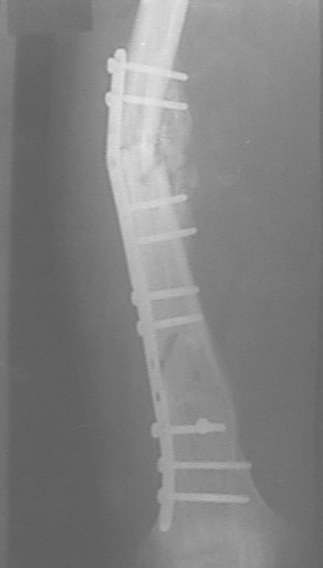

Re: Неправильно сросшийся перелом голени

Александр Николаевич, к сожалению больной не является на контрольные осмотры. Я последний раз видел больного, когда прошло 7 месяцев после операции БОС. У него все хорошо. Каких либо жалоб и ограничений в нагрузке нет. Высылаю снимки до операции и последние снимки.